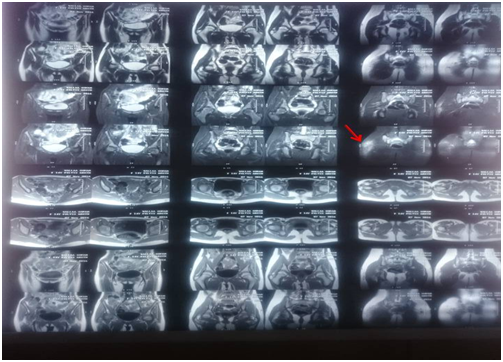

15 yrs old female patient born and lives in Kafr Elsheikh, Egypt was diagnosed to have typical attacks of FMF 5 years ago on colchicine treatment (1.2 mg/d), Molecular genetic study revealed positive heterozygous state , MEFV gene mutations (M694V , E148Q , P369S). The patient has positive family history (her father and uncle has FMF), During the past 6 months, the patient experienced bilateral diffuse, non exertional crippling muscle ach with swelling of both thighs restricting movement of lower limbs, not relieved by colchicin or NSAIDS, the condition was not associated with fever and colicky abdominal pain or skin rash for which she was admitted in the hospital of the faculty of medicine Alex University where initial examination and investigations were done then the patient sought a medical advice in our department. On systematic physical review: The well-developed patient was bedridden in agony normal blood pressure and temperature. Height=145 cms, weight=40 kgs, BMI=19. There was bilateral symmetrical diffuse& tender swelling of both thighs with subcutaneous edema made her unable to move the lower limbs properly, sensory and motor exam of the upper extremities was normal, Cardiac, chest, abdominal examination was apparently free. Laboratory investigations revealed normal levels of CK, CK-MB, Aldolase & transaminases. Hemoglobin 13.8 g/dL; white blood cell count 5000/mm3, platelet count, 209,000/mm3; ESR was 14mm/h and high C-reactive protein (CRP) (40 Iu/L). Normal liver & kidney function tests. ASOT within normal range (150 U/ml), ANA, ANC, RF & amyloid A were negative virology markers for HCV, HBV& CMV. Chest X-ray, Abdominal ultrasonography, bilateral lower limb arterial and venous duplex & Ultrasound knee joint showed no abnormalities. MRI of both thigh on presentation showed right posterolateral thigh ill defined patchy area of soft tissue edema involving subcutaneous tissue eliciting high signal in STIR & measure about 10 cm, normal MR musculature appearance with intact intermuscular fascial fat planes (Figure 1)(Figure 2).

MRI can be considerd as a valuable tool to diagnose PFMS, the features that suggest PFMS are diffuse oedema of subcutaneous fat tissue, increased intensity and contrast enhancement of the muscles and increased signal intensity of vascular beds.15 Electromyogram (EMG) may be normal or show nonspecific myopathic changes, Muscle biopsy was not feasible in most of diagnosed cases, but of which was done revealed non specific inflammatory inflilteration with leucocytes, lymphocytes and eosinophills.

It was peculiar that our young lady case presented with atypical attack of FMF consisting of severe muscle pain & swelling affecting both thigh but not accompanied by fever, rash or abdominal pain o. Also ESR was not elevated as excepected there is no definite rational for that; yet the compliance of the patient to colchicine may abort the elevation of ESR as acute phase reactant. We began to revise the history and to put differential diagnosis. Myopathy related to FMF was on the top after exclusion of vasculitis. Hence Fulfiling the clinical criteria, normal CPK levels & characteristic MRI findings (oedema of subcutaneous fat tissue) together with the evidence of inflammatory myopathy by EMG are the hallmarks of diagnosing PFMS and excluding out the colchicines induced myopathy. Immediately, the decision was made based on the foregoing & Steriods were prescribed with collaporation of physiotherapy team for more than 2 months a good response was achieved and the patient was able to move independently